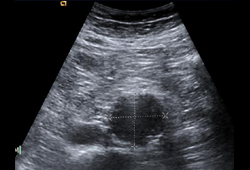

Ultrasonido de un AAA de 3.8 cm x 4.2 cm

University of Michigan, específicamente los casos del Dr. Upchurch que reflejan los Departamentos de Cirugía Vascular y Radiología